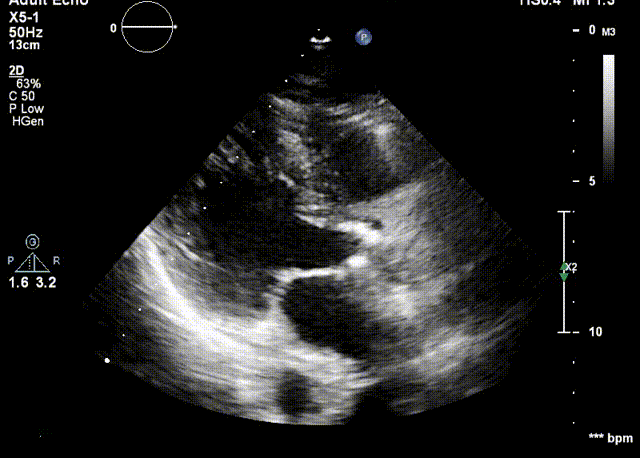

检查结果-术中超声

检查结果-即刻超声

动脉瓣瓣周轻度反流。

经主动脉口收缩期血流最大速度约1.5m/s,最大跨瓣压差约10mmHg。